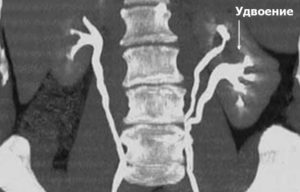

Двухстороннее удвоение, по статистике, встречается всего в 10% случаев этой патологии. Почка может быть удвоена полностью или частично. Патологическая почка имеет значительно больший размер по сравнению с нормальной.

Неполное удвоение почки встречается намного чаще, чем полное (80-90% случаев). При этом почка заметно увеличена. Каждую часть такого органа питает отдельная почечная артерия, но ЧЛС его единая. Иногда ЧЛС развивается две, а питает их одна артерия.

Удвоение почки – врожденное изменение мочеполовой системы (МС), проявляющееся развитием дополнительной почки с одной или двух сторон. Аномалия может иметь вид отдельного органа, нароста или отдела в здоровой почке.

Частичное удвоение — это разновидность удвоения органа, которое характеризуется особенностью структуры и строения органа, когда удвоение сосудов и почечной паренхимы производится без раздвоения лоханок. Получается, что синус почки делится перемычкой из паренхимы на два обособленных отдела. Подобное деление провоцирует увеличение размеров органа.

Что это такое? Это разделениеоргана на две половинки, сросшиеся между собойполюсами. Каждая часть снабжена собственной системой кровоснабжения. Внешне такая почка значительно больше по размерам.

Эта патология наблюдается, когда у человека формируется одна большая почка с четко обозначенными верхним и нижним отделами. Каждый из них имеет свою почечную артерию. Н, каждая часть удвоенного органа не имеет собственной чашечно-лоханочной системы, она у них одна на два отдела. Мочеточника два, но они соединены между собой и в мочевой пузырь впадают единым стволом, как один.